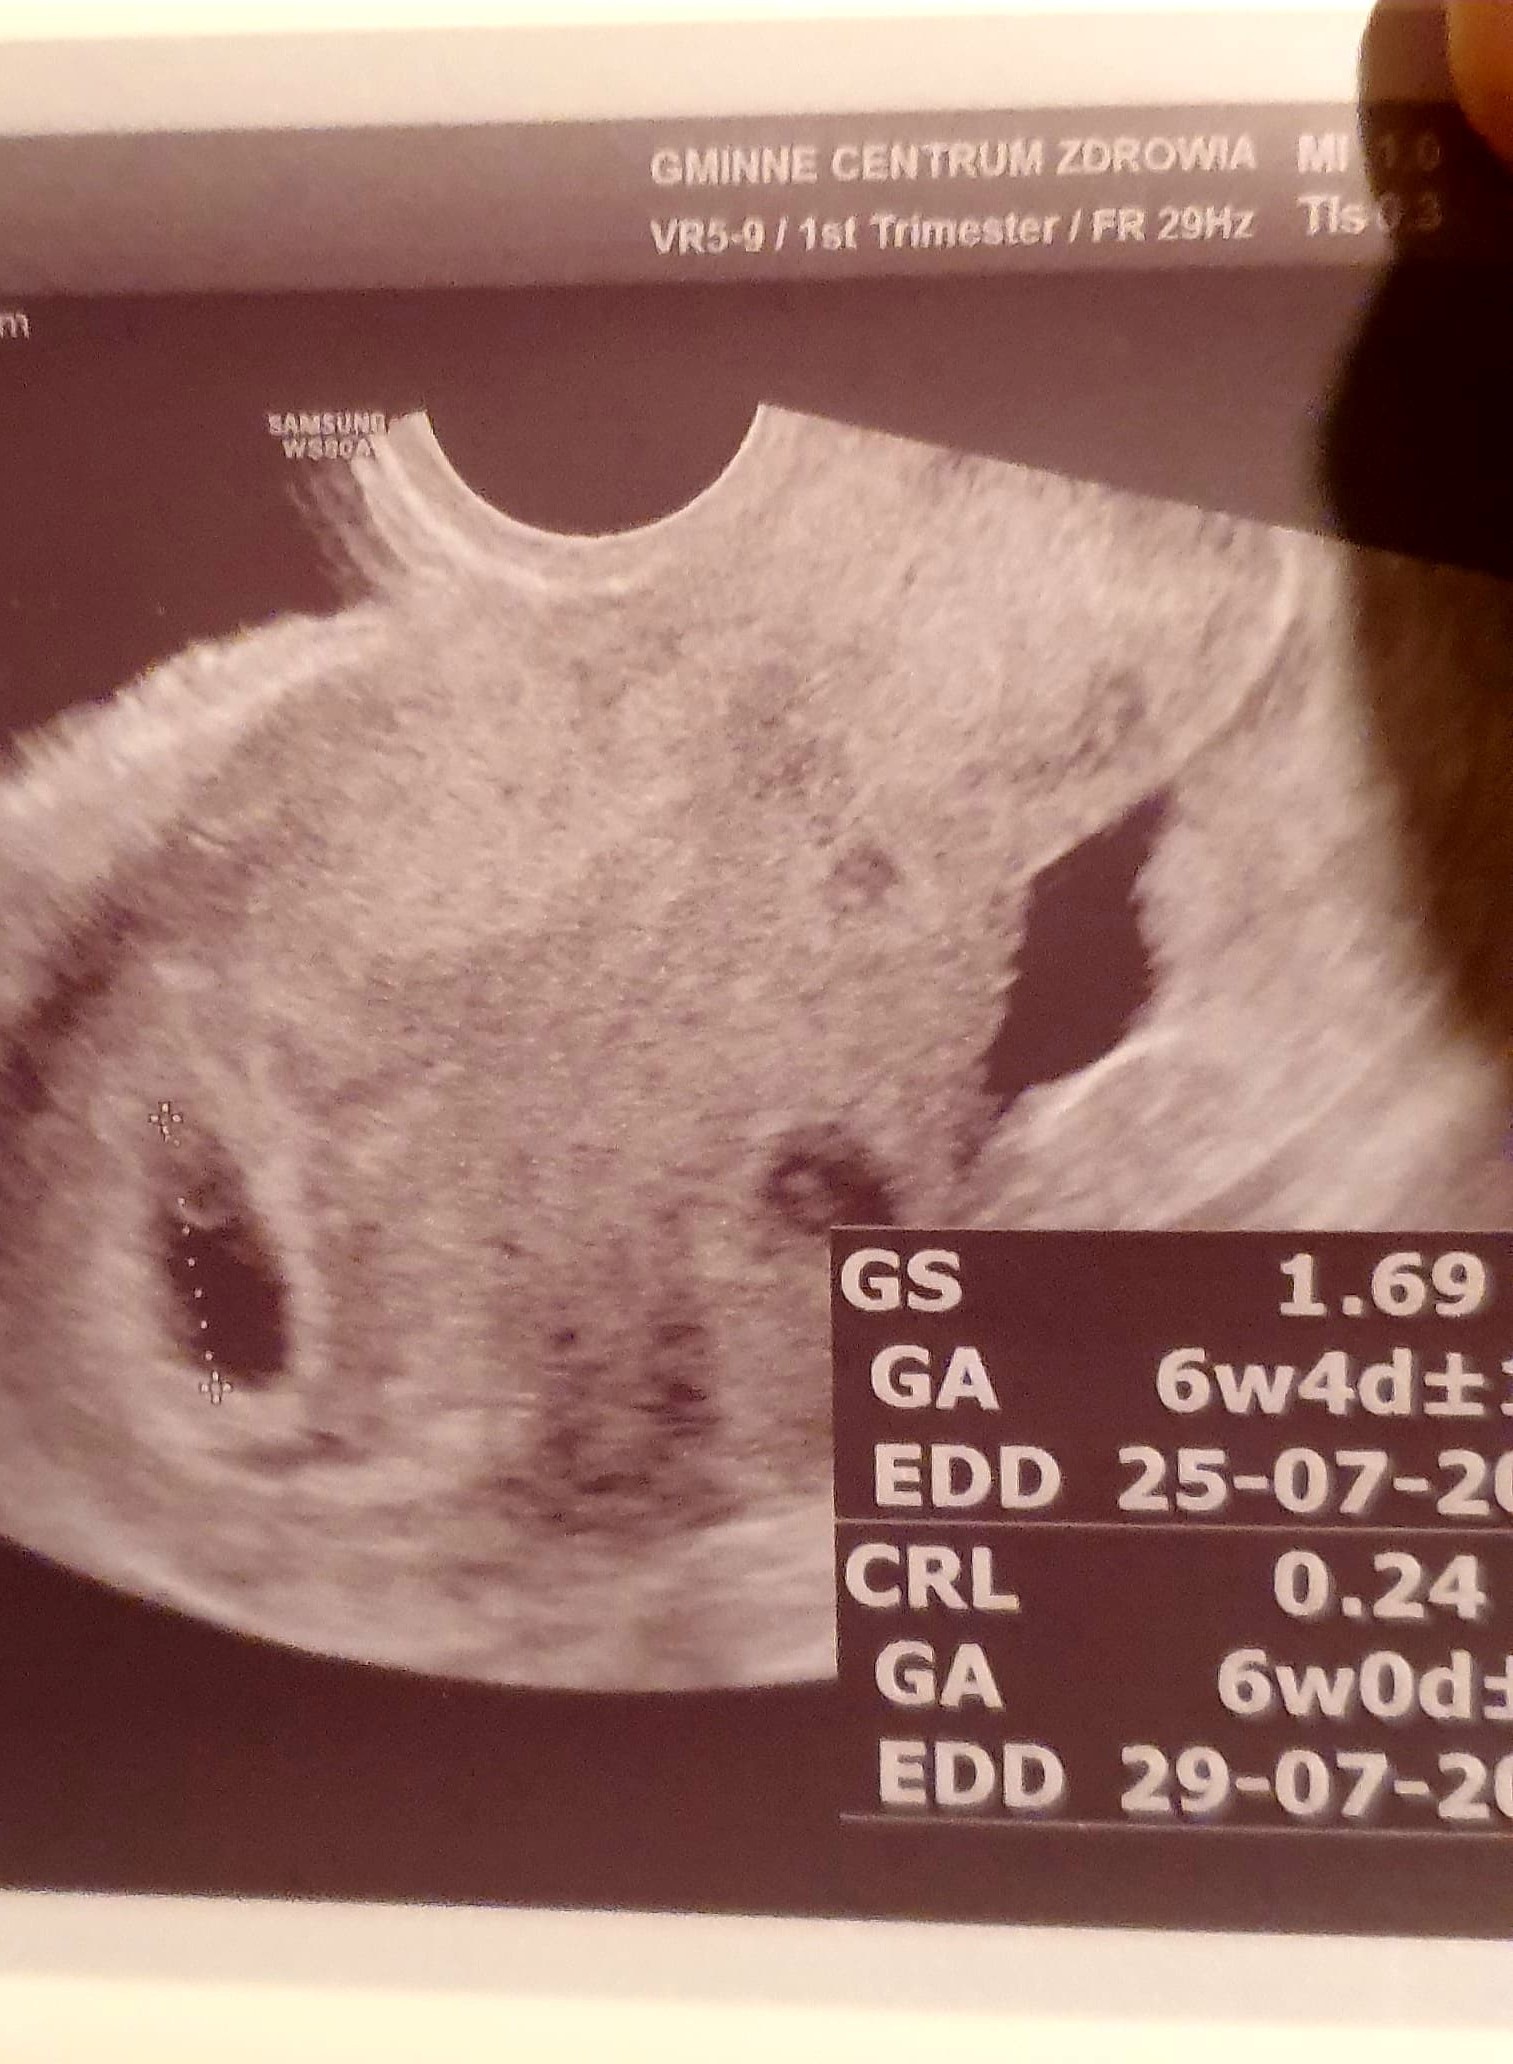

Czy to ciążą bliźniacza?

Witam, proszę o pomoc w kwestii usg, czy to ciąża bliźniacza? 6tc

Hmm tak wygląda jakby dwa pęcherzyki i zarodki ,a lekarz nie mówił że bliźniacza ?

Lekarz zrobił tylko szybki pomiar i kazał przyjść w poniedziałek. Wystraszyłam się kiedy spojrzałam na zdjęcie po wyjściu od lekarza, bo to moja 4 ciąża i żadna tak na początku nie wyglądała. Plus jeszcze dwa pomiary, i tak nie śpię od środy przez to, dlatego pytam

Nie martw się ,w poniedziałek wszystko się wyjaśni ,dopytaj lekarza żeby potem nie myśleć,sama nie wiem ,skoro lekarz nie wspomniał że są dwa zarodki to może to nie bliźniak ..nic nie wymyślę niestety ,ale ten większy pęcherzyk wygląda dobrze ,jest zarodek